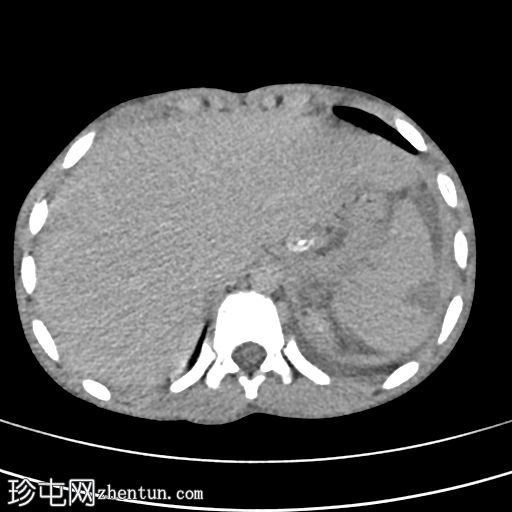

增强扫描(动脉期)

1.jpg

脾脏显示弥漫性实质损伤(根据美国创伤外科协会(AAST)脾脏损伤分级标准,为IV级损伤)。脾脏实质内可见一灶性造影剂聚集,提示脾内出血而非脾外出血。

腹腔内可见轻度高密度液体,符合血腹表现。

左侧可见轻至中度胸腔积液。

影像学表现符合IV级脾脏损伤。